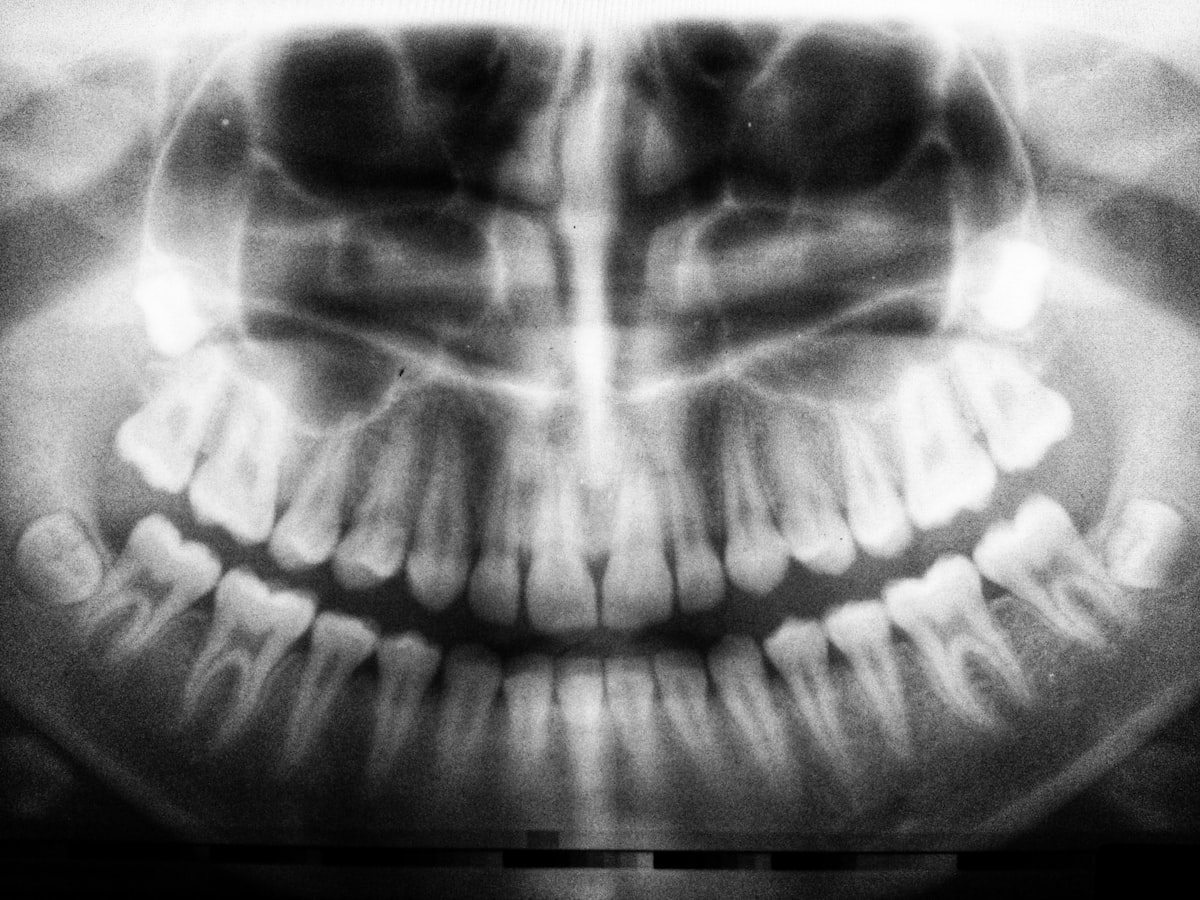

Ortopantomografia panoramica dental digital Minas

Ortopantomografia (OPT)

Radiografia panoramica digital de ambas arcadas, maxilares, ATM y estructuras adyacentes en una sola toma. El estudio mas solicitado por odontologos.